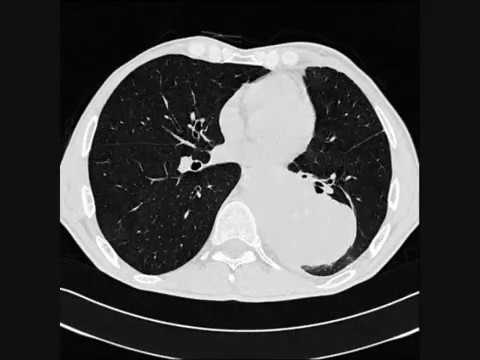

Для количественной оценки и классификации эмфиземы легких необходима КТ. Центролобулярная эмфизема (а) характеризуется мелкоузелковыми просветлениями, соответствующими раздутым альвеолам в центре ацинусов. Для панлобулярной эмфиземы (с) характерны генерализованная воздушность и деструкция легочной паренхимы. Часто встречаются переходные формы (b) между центролобулярной и панлобулярной эмфиземой. Парасептальная эмфизема наблюдается часто и обычно не имеет клинического значения (d). На представленных томограммах она сочетается с центролобулярной эмфиземой.

Что покажет МСКТ грудной клетки при эмфиземе

- Парасептальная эмфиземе легких — буллезная

- Поражаются преимущественно базальные сегменты легкого

- При панлобулярной эмфиземе легких нарушается архитектоника всей дольки

- При центролобулярной эмфиземе легких отмечается деструкция стенки альвеол в центре вторичных легочных долек, периферические отделы долек и сосуды интактны

- Участки повышенной рентгенопрозрачности (эмфиземный порог составляет менее -950 HU; нормальная плотность легочной ткани находится в пределах от -750 до -900 HU).

- Поражаются преимущественно краниальные сегменты легкого.

- Сосудов становится меньше

- Особая форма панлобулярной эмфиземы развивается при недостаточности a1-антитрипсина.

- Преимущественно затрагивает субплевральные и бронховаскулярные участки легкого.